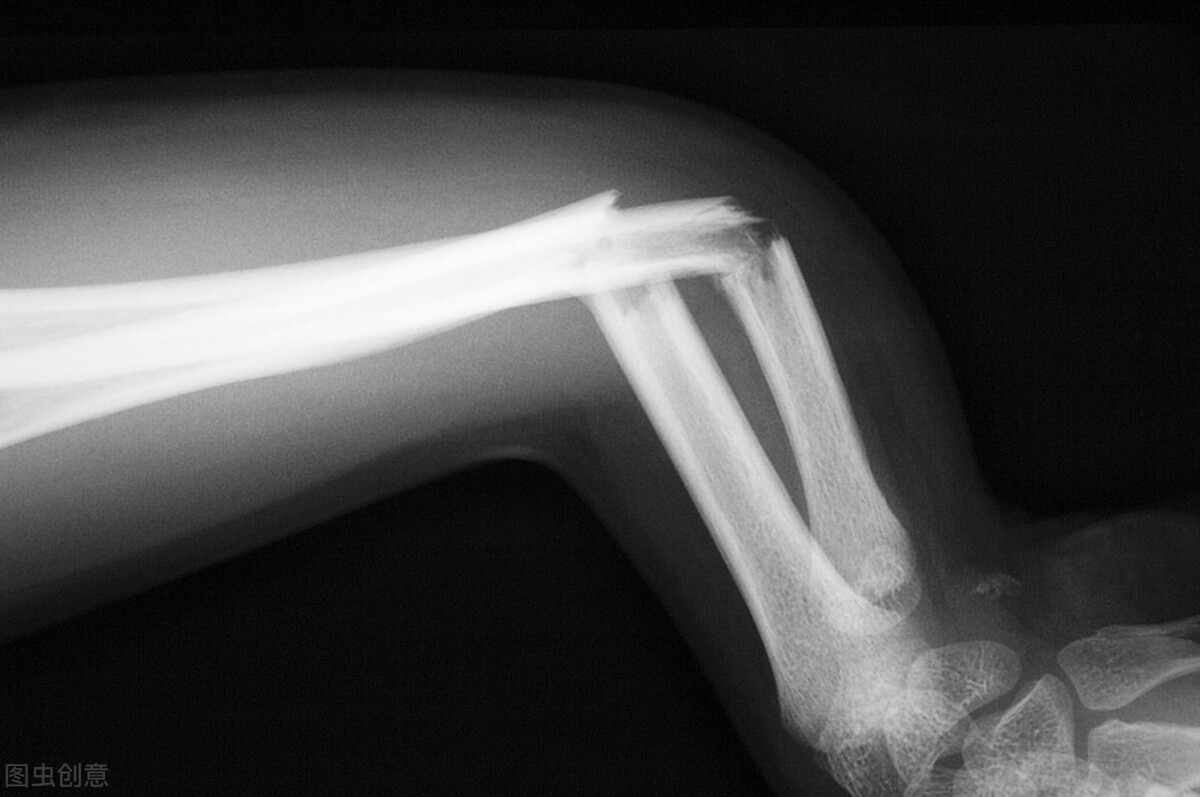

骨折病人吃什么好得快和禁忌(骨折后吃什么能够加速愈合,长得更好?医生总结出4类,实测有效)

骨骼是人体的结构担当。它所支撑起来的人体轮廓和空间架构,给其他器官提供了庇护场所和力量支撑。

一旦骨头受伤发生骨折,除了骨折处疼痛之外,还会限制我们的活动。

正所谓伤筋动骨一百天,骨折后需要较长时间的恢复期。除了遵循医嘱服药、康复之外,若能科学饮食,也会加速骨骼愈合,防止再次骨折。

骨折后,会经历“血肿期+骨痂形成期+愈合期”这几个阶段。但总的来说是成骨细胞在辛勤工作的过程。